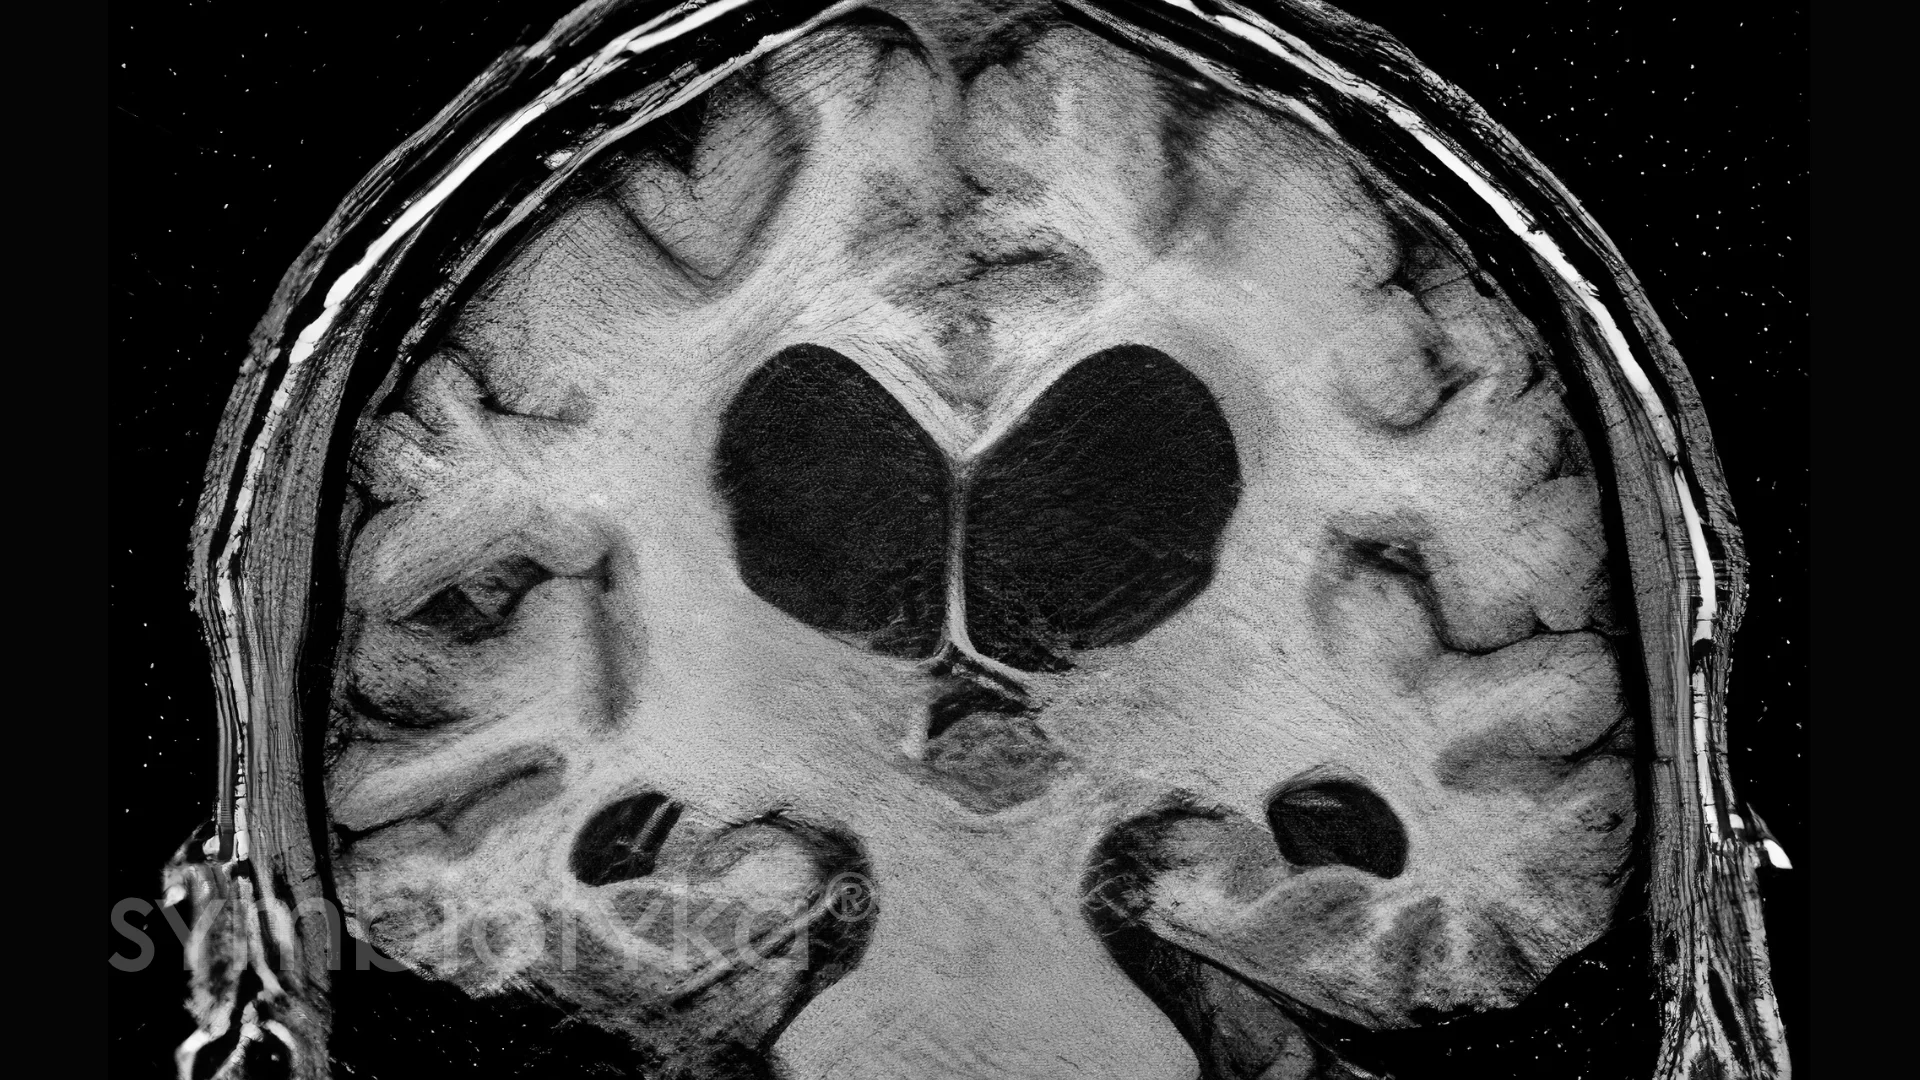

Магнітно-резонансна томографія (МРТ) — основний метод діагностики пінеоцитоми.

Переваги МРТ:

Пінеоцитома зазвичай виглядає як добре відмежоване утворення, яке помірно накопичує контраст.